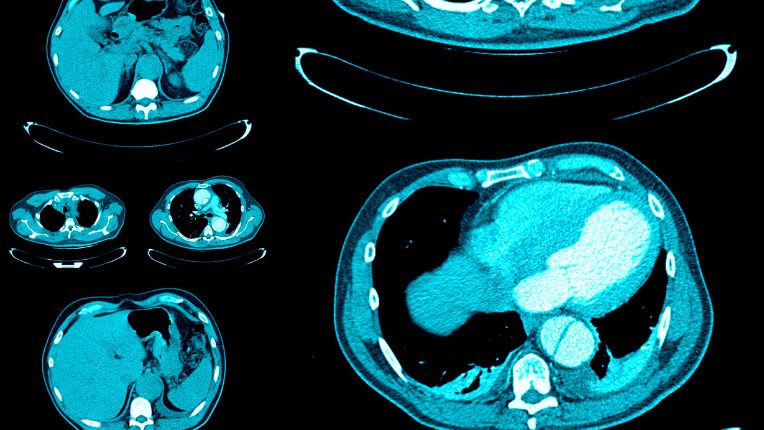

Scanner thoracique

Le scanner thoracique est un examen d’imagerie médicale qui consiste à explorer le thorax aux rayons X. Il permet d’observer les poumons, le cœur, la plèvre, les vaisseaux sanguins, la glande thyroïde, les ganglions lymphatiques et les côtes. Découvrez en quoi consiste un scanner du thorax et quelles sont ses indications. Mais aussi comment il se déroule et comment interpréter ses résultats.

Le scanner thoracique, ou scanner du thorax, désigne un examen d’imagerie médicale destiné à explorer la cage thoracique. Grâce à l’émission de rayons X, le scanner thoracique permet de visualiser sur un écran d’ordinateur des images en coupe d’une grande précision. Le médecin peut alors observer l’état des poumons, de la plèvre, du cœur, des vaisseaux sanguins (artère pulmonaire, artères coronaires), des vaisseaux lymphatiques ou encore de la glande thyroïde et des os (sternum, côtes). La prescription d’un scanner du thorax peut répondre à divers objectifs médicaux. Elle est effectuée seule ou en complément d’autres examens.